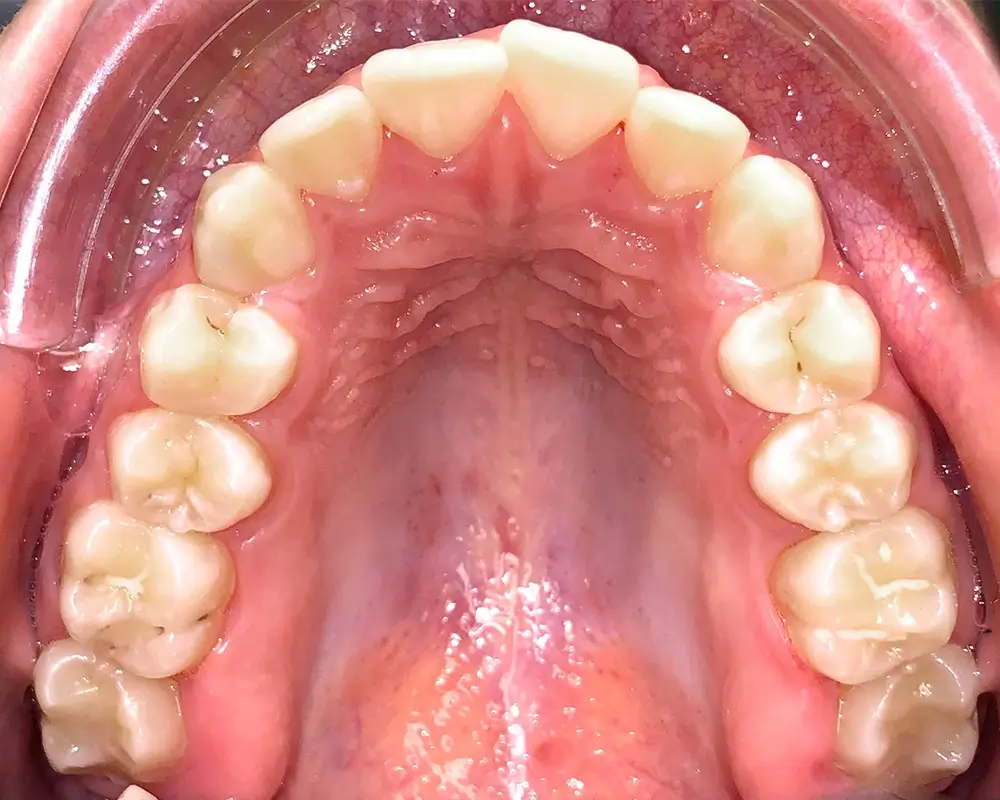

Скученность - Кейс 16

Эффективность устранения дефекта прикуса посредством элайнеров FlexiLigner.

20

Количество кап НЧ

Количество кап ВЧ

Результаты лечения